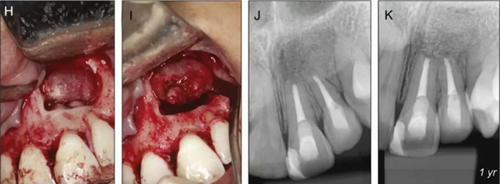

圖5. 翻瓣后將根尖區(qū)病理組織及21、22根尖完整切除,切除組織立即置于10%福爾馬林中固定。牙根倒預(yù)備、充填,植骨蓋膜。

圖6. 病例組織大體圖及X線片